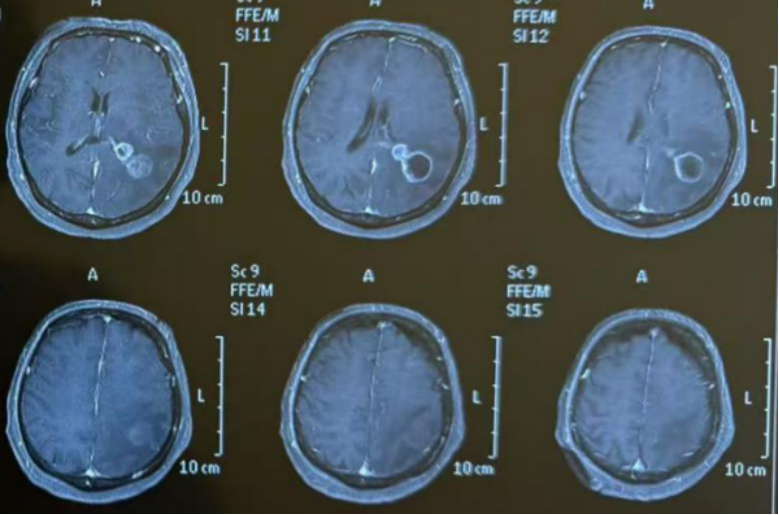

治疗过程中,陶荣杰教授神经肿瘤团队密切监测疗效,在其为高女士“量身定制”的“整合治疗”方案下,高女士脑肿瘤发展得到有效抑制,身体及精神状况逐渐好转。

基因突变虽然让病情变得复杂,但树兰(济南)医院神经肿瘤科陶荣杰教授团队通过精准化诊断、个体化治疗,让每一位患者及其家人看到了希望的曙光。